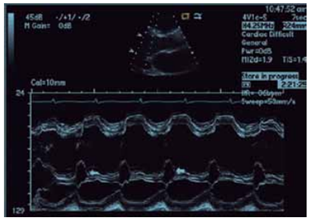

Observe a imagem.

A imagem sugere a presença de

Médico - Ecocardiografia